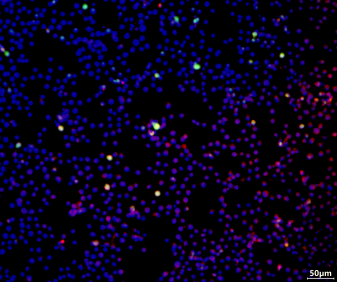

Immunofluorescence results show that the drug can significantly enhance macrophage M2 polarization and inhibit M1 polarization.